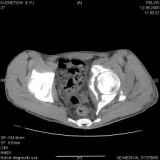

Уважаемые коллеги! Хотелось бы услышать совет по тактике лечения представлленого больного.Поступил после лечения в одном изотделений области. Травма 2,5 месяца назад. После выведенияиз шока был произведен остеосинтез перелома бедра, предплечья, до перевода к нам проводилосьвытяжение по оси шейки бедра за стержень, введенный в большой вертел. На сегодня деформацияригидна, клинически мобильности не определяется. Заранее признателен. P.S. Данный вид травм не включен в перечень "высокотехнологичных операций", направить длялечения по квотам Минздрава очень сложно.

Это обзорные и косые снимки

С уважением,

Leonid